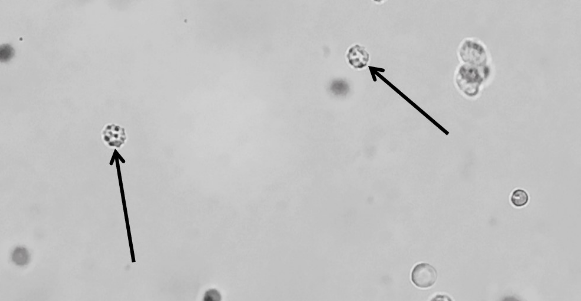

原蟲(chóng)